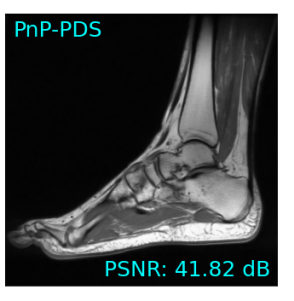

Single-coil results: Table 1 shows that D-GEC outperformed D-VDAMP in all single-coil experiments and outperformed PnP-PDS in all but SSIM at . Figure 5 shows an example of the wavelet coefficients input to D-GEC’s denoiser at the 10th iteration, and their error relative to the true coefficients. Figure 3 shows the evolution of the standard deviation at the input to D-GEC’s denoiser in each subband; there is a good agreement between true and predicted values. Figure 6 suggests that the subband errors are Gaussian. Figure 4 shows image recoveries and error maps for one test image at .

Multi-coil results: Table 1 shows D-GEC significantly outperforming PnP-PDS in PSNR and SSIM in the 4-coil case. D-VDAMP does not support multi-coil recovery and thus is not shown.